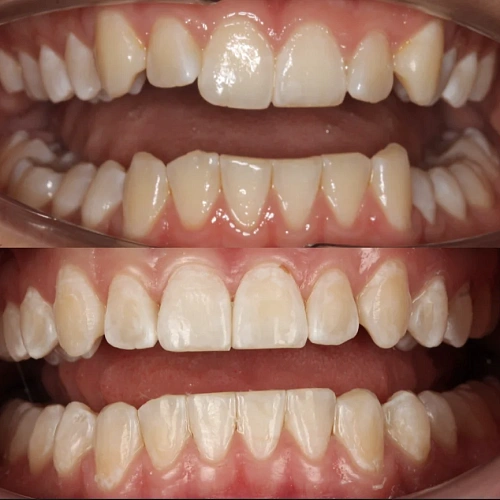

Нарушение соотношения челюстей и неправильное положение зубов — зубные ряды смыкались некорректно, зубы стояли со смещением.

Прозрачные элайнеры Invisalign на обе челюсти. Выровнять зубы и нормализовать смыкание. Срок — около 2 лет.

Лечение заняло 4 года (февраль 2022 — март 2026). Капы менялись каждые 1–2 недели, визиты к ортодонту для контроля и выдачи новых наборов.

Зубы выровнены, смыкание нормализовано. Установлены несъёмные ретейнеры на обе челюсти. Пациент направлен к ортопеду.

Проблема: В клинику обратился мужчина с жалобами на неправильное положение зубов и смыкание — ряды сходились некорректно, зубы стояли со смещением. При этом было важно, чтобы лечение оставалось незаметным для окружающих, поэтому вариант с брекетами не рассматривался.

Решение: Поставили элайнеры Invisalign на обе челюсти. Лечение заняло 4 года — случай потребовал нескольких этапов коррекции, каждый из которых последовательно приближал зубы к нужному положению. Капы менялись каждые 1–2 недели, контрольные визиты — для отслеживания прогресса и выдачи новых наборов. Зубы встали на место, смыкание пришло в норму. Зафиксировали ретейнеры на обе челюсти, пациент направлен к ортопеду для завершающего этапа.